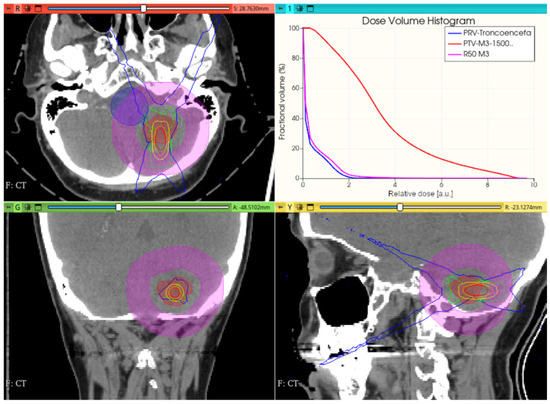

3.3.1. Preliminary CONVERAY Dosimetry Performance for Intracranial Irradiations